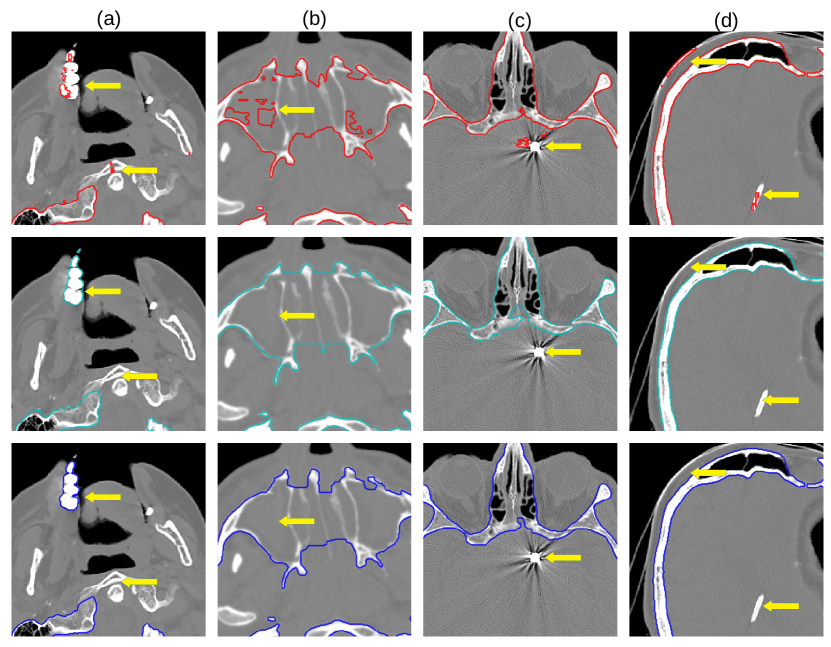

22 scans were randomly selected as test subjects for the experiment, leaving 177 skulls for model training. Using convolutional kernels of size 3 in all the CNN models results in the 3D model having the same number of trainable parameters as the sum of the three orthogonal 2D models. The comparison between the MV ensemble and the 3D approach can therefore be considered an ablation study to an extent. CutCNN models also have a similar number of parameters, the only difference being the final edge probability output layer. Quantitative comparison of results of each method are presented in Figure 4 and Table 1. Further qualitative results are shown in Figure 5 and 1.

CutCNN segmentation framework resulted in a performance gain in all cases in terms of every metric used in the experiment over standard CNN approaches. The output of CNN object probability map often contains errors near external objects or smaller tissue defects as these are scarce in the training data distribution. However, the graph-cut optimization guides the resulting binary segmentation towards a spatially consistent and compact shape, often eliminating these artifacts if a detected edge corresponds mostly to the correct object boundary. This effect is further illustrated in Fig. 1.

Our second observation is that using 3D convolutional kernels has a rather small effect on the final segmentation precision quantitatively compared to the MV approach. However, although the quantitative difference is small, for applications in medical additive manufacturing, it is important to avoid ragged segmentation output which may result from MV CNN in areas of lower model certainty. These include for example teeth, which are challenging to detect, especially when the lower and upper teeth are in contact (see Figure 5 a), or maxillary sinus, which is often enclosed in order to improve mechanical stability of the manufactured model (see Figure 5 b). Therefore, 3D U-nets are often considered necessary to avoid these discontinuities caused by slice-by-slice processing.

However, this artifact can also be addressed by employing the CutCNN framework since ragged segmentation boundary introduces a high boundary-term penalization during optimization and it is therefore avoided in the final binary segmentation. Thus, employing CutCNN allows the decision between 3D or multi-view approach to be merely a technical choice. Using 2D models can offer some advantages, such as faster training of deeper models with less overfitting [10].